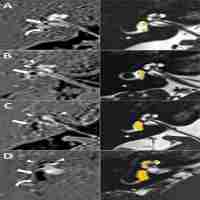

| Abstract | OBJECTIVES In this study, we aimed to investigate whether the symptoms of vertigo related to hypertension resulted from endolymphatic hydrops and the efficacy of the thiazides in the treatment. PATIENTS AND METHODS A total of 24 vertigo patients without peripheric or central vestibular pathologies or hyperlipidemia were included. The study group comprised 15 patients with hypertension, including nine with regulated non-insulin-dependent diabetes mellitus (DM). The control group comprised nine patients without hypertension or DM. The patients in the study group received hydrochlorothiazide treatment. The European Evaluation of Vertigo Scale (EEVS) and Vertigo Handicap Questionnaire (VHQ), puretone audiometry, tympanometry, electronystagmography (ENG) for nystagmus tests, oculomotor tests, and caloric test were carried out initially and at three weeks for both groups. The results of the study group were compared to those of the control group. RESULTS There was a statistically significant decrease in the scores of EEVS and VHQ at three weeks in the study group, compared to the baseline scores (for both groups p≤0.01). CONCLUSION Our study results showed that thiazides alleviated vertigo symptoms in hypertensive patients, as measured by qualitative methods (i.e. EEVS, VHQ), but not with quantitative measurements (i.e. ENG). |